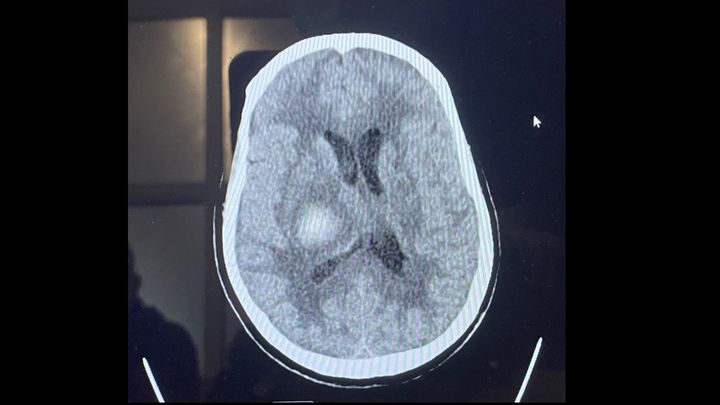

Adela Rodriguez Deras suffered from a stroke on Thursday February 3rd, 2022. After 28 days of slow and steady progress as well as preparation to leave the ICU and move into an acute care facility where there was hope for her to gain the strength to come home, she suffered from another severe stoke. Adela fell into a coma at 3:33 am on Thursday March 3rd, 2022. The amount of pressure in her cranium was too much for her to bare and left our loving Adela brain dead.